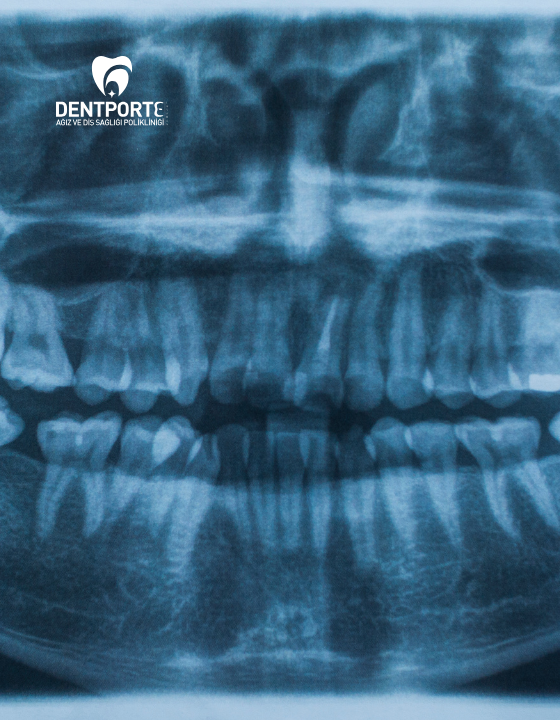

Panoramik Röntgen

Panoramik Film Hizmeti

Tüm Ağız Yapısını Tek Bir Görüntüde İnceleyin

Panoramik röntgen, tüm ağız yapısını tek bir görüntüde gösteren, kapsamlı bir diş ve çene incelemesi sunan bir radyografi yöntemidir. Çene kemiği, dişler, gömülü dişler ve çevre dokuların fizyolojik ve patolojik durumlarının değerlendirilmesi için tercih edilir.

Panoramik Röntgen Nasıl Çekilir?

•Hasta cihazın baş ve çene kısmına yerleştirilir.

•Baş çevresinde dönen cihaz, görüntüyü bilgisayara aktarır.

•İşlem kısa sürede tamamlanır ve ağrısızdır.

Panoramik Röntgen Zararlı mı?

•Radyasyon seviyesi oldukça düşüktür ve modern cihazlarla bu oran minimuma indirilmektedir.

Her iki röntgen türü de diş ve çene sağlığı için önemli teşhis araçlarıdır. Tedavi planının doğru belirlenebilmesi için hekim önerisine göre uygun röntgen türü tercih edilmelidir. Hamile hastalarda radyografi çekimi önerilmez, ancak acil durumlarda koruyucu önlemler alınarak yapılabilir.